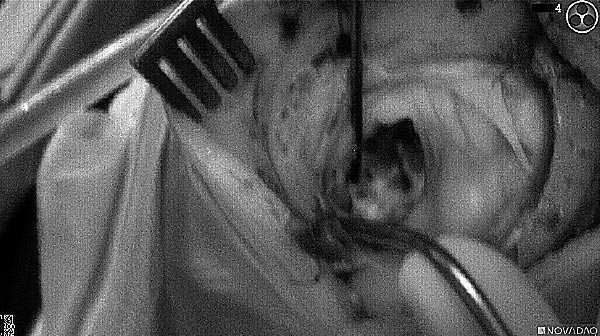

Intraoperative imaging panitumumab-IRDye800 (fluorescence)

Primary tumor prior to resection

Wound bed post re-resection of tumor

Fluorescence imaging of the tumor was performed prior to resection and after resection to “check” the wound bed. In the upper row the tumor is clearly visible with fluorescence and in the bottom row you can see that the wound bed is empty – there is no suspicious fluorescence left. The middle column of tiles show the fluorescence signal in black and white where the “white” represents the tumor and the black the background (= no fluorescence signal). The right column of tiles shows the overlay of the brightfield photo (in greyscale) and the fluorescence (red-yellow-blue heatmap). This image provides anatomical context to the surgeon – the surgeon can see where is the fluorescence located with regard to the tumor area.